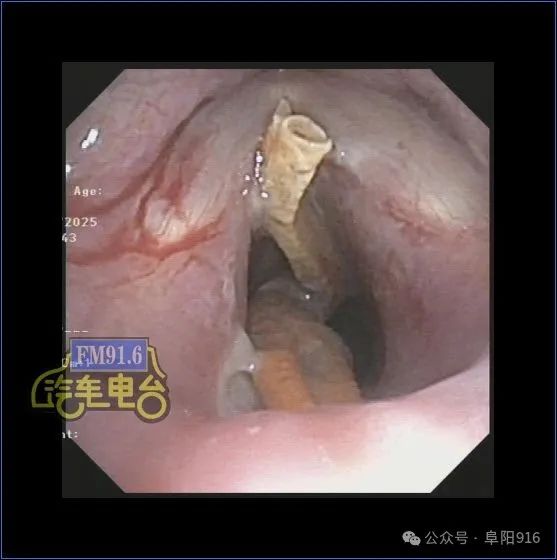

随后,徐女士立即被收治入院。医生在电子支气管镜下发现,龙虾钳横卡在声带与气管上端之间,声带无法闭合,局部已出现出血、溃疡,随时可能引发声带撕裂或气管穿孔。经过多次尝试,医生最终成功取出这枚长约4厘米左右的龙虾钳。